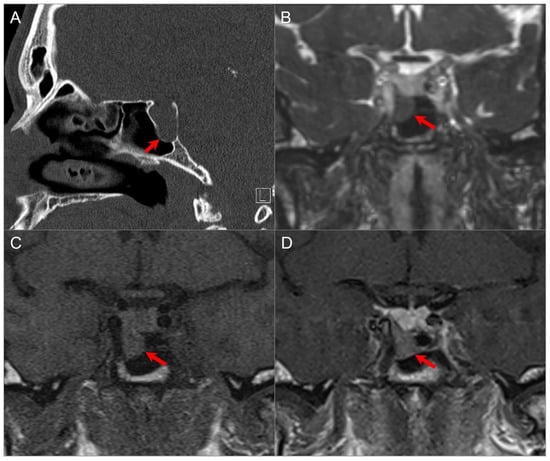

5.7. Petrous Apex Trapped Fluid